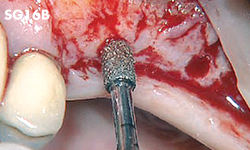

Fenestración y conformación del hueso.

• POTENCIA [SURG] 80%

• Revestimiento de diamante

Fenestración y conformación del hueso.

• POTENCIA [SURG] 50%

• Revestimiento de diamante